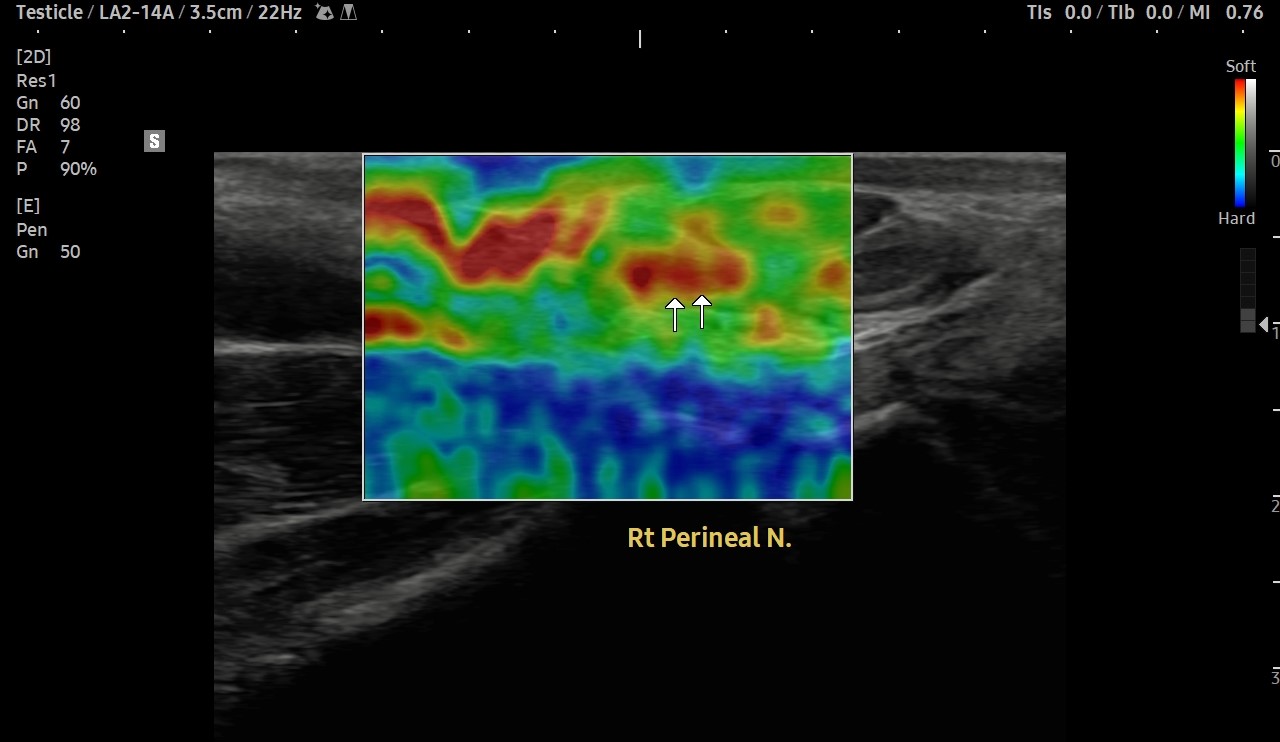

[치료 전]

[치료 후]

- 치료횟수 : 20 회